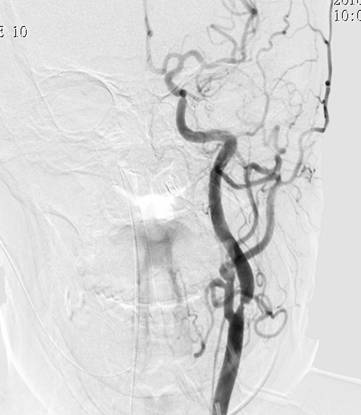

1周前,郭大姐再次发生右侧肢体无力的症状,于是家人将她送到广东三九脑科医院神经内科就诊,入院后积极完善相关检查,颅脑DWI显示:1、左侧基底节区、大脑脚及桥脑右侧、右侧枕叶多发陈旧性脑梗塞,2、考虑胼胝体压部偏左侧脑梗塞(偏慢性期)(如图1、图2)。DSA检查提示:1. 基底动脉末端闭塞,双侧大脑后动脉、后交通动脉未见显影,双侧大脑中动脉经皮层软膜动脉向同侧枕叶代偿供血;2. 双侧颈内动脉起始部重度狭窄(如图4、图5),狭窄率约90%,狭窄长度约20px;3.双侧椎动脉起始部中度狭窄,狭窄率约50%;4. 脑动脉硬化,颅内动脉走行僵硬,呈不同程度狭窄。

图 4 术前DSA提示:左侧颈内动脉起始部放大;